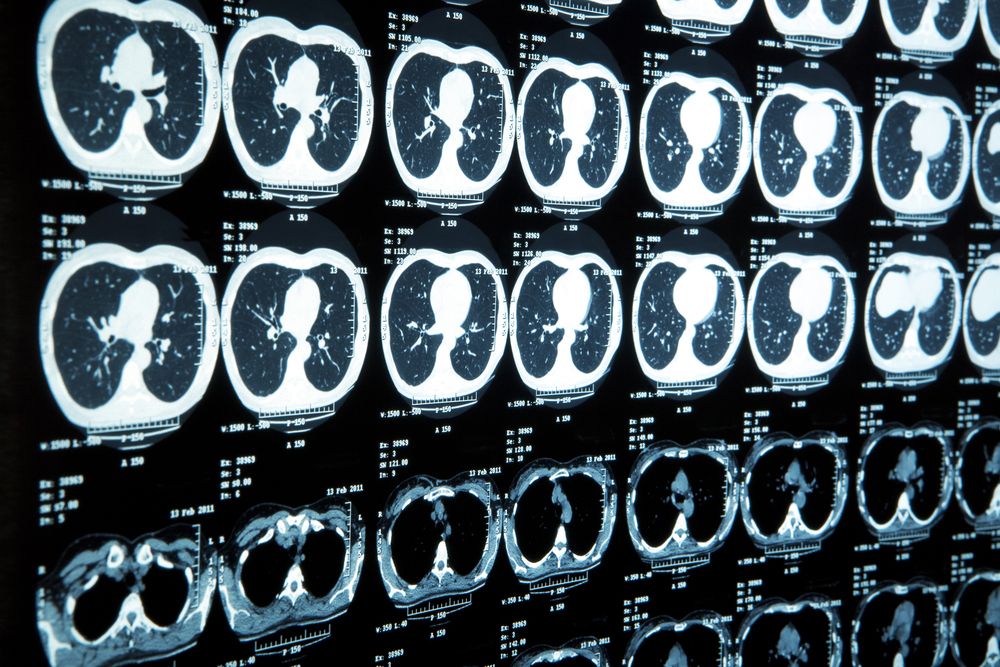

Fewer CT scans are needed for trauma patients when whole-body CT is included in early trauma care, but initial WBCT results in higher dose.